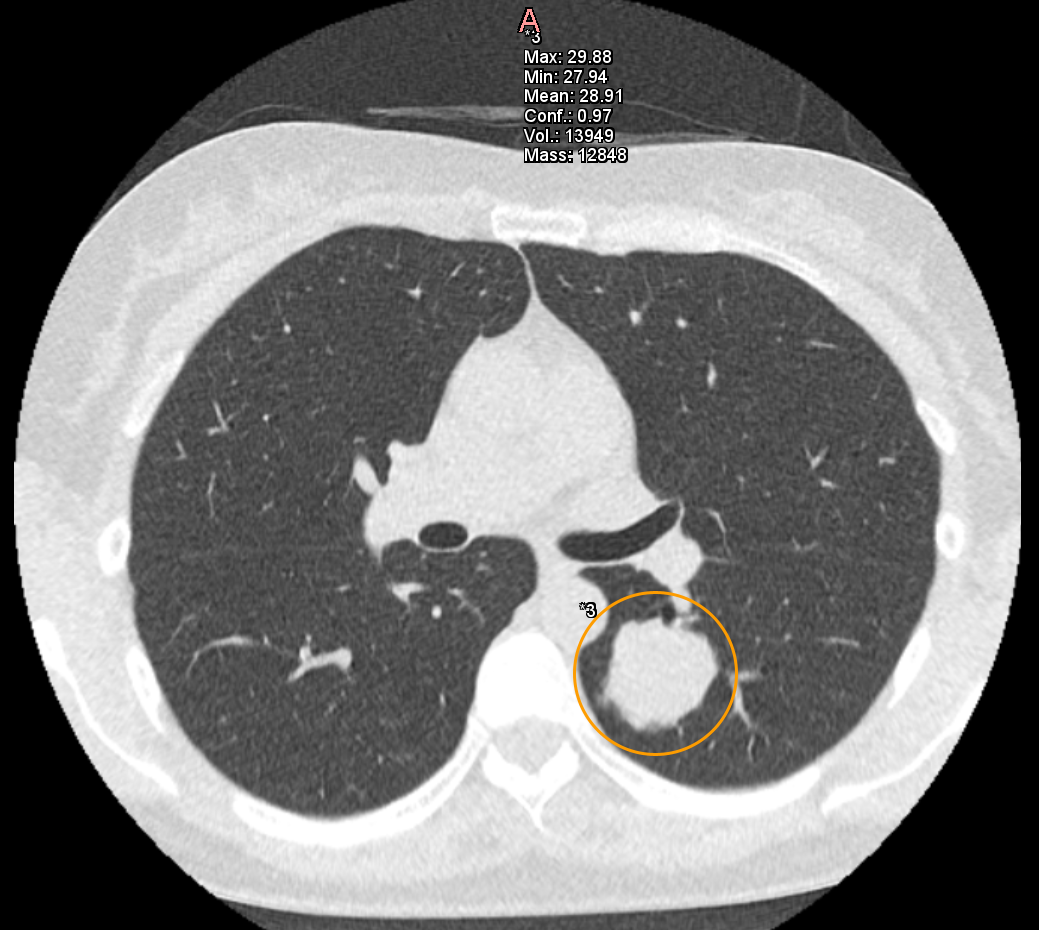

また、胸部X線AI「Plus.CXR」では著者が通常は指摘できない、径5mm前後の比較的小さな病変を指摘できます。

加えて、肺門部周囲の太い血管陰影とシルエットが明瞭に存在する淡い透過性の低下部を指摘することができました。これらは、十分な集中力で画像を参照していない場合見落とす可能性が高い所見だと思料されます(図1,2,3)。